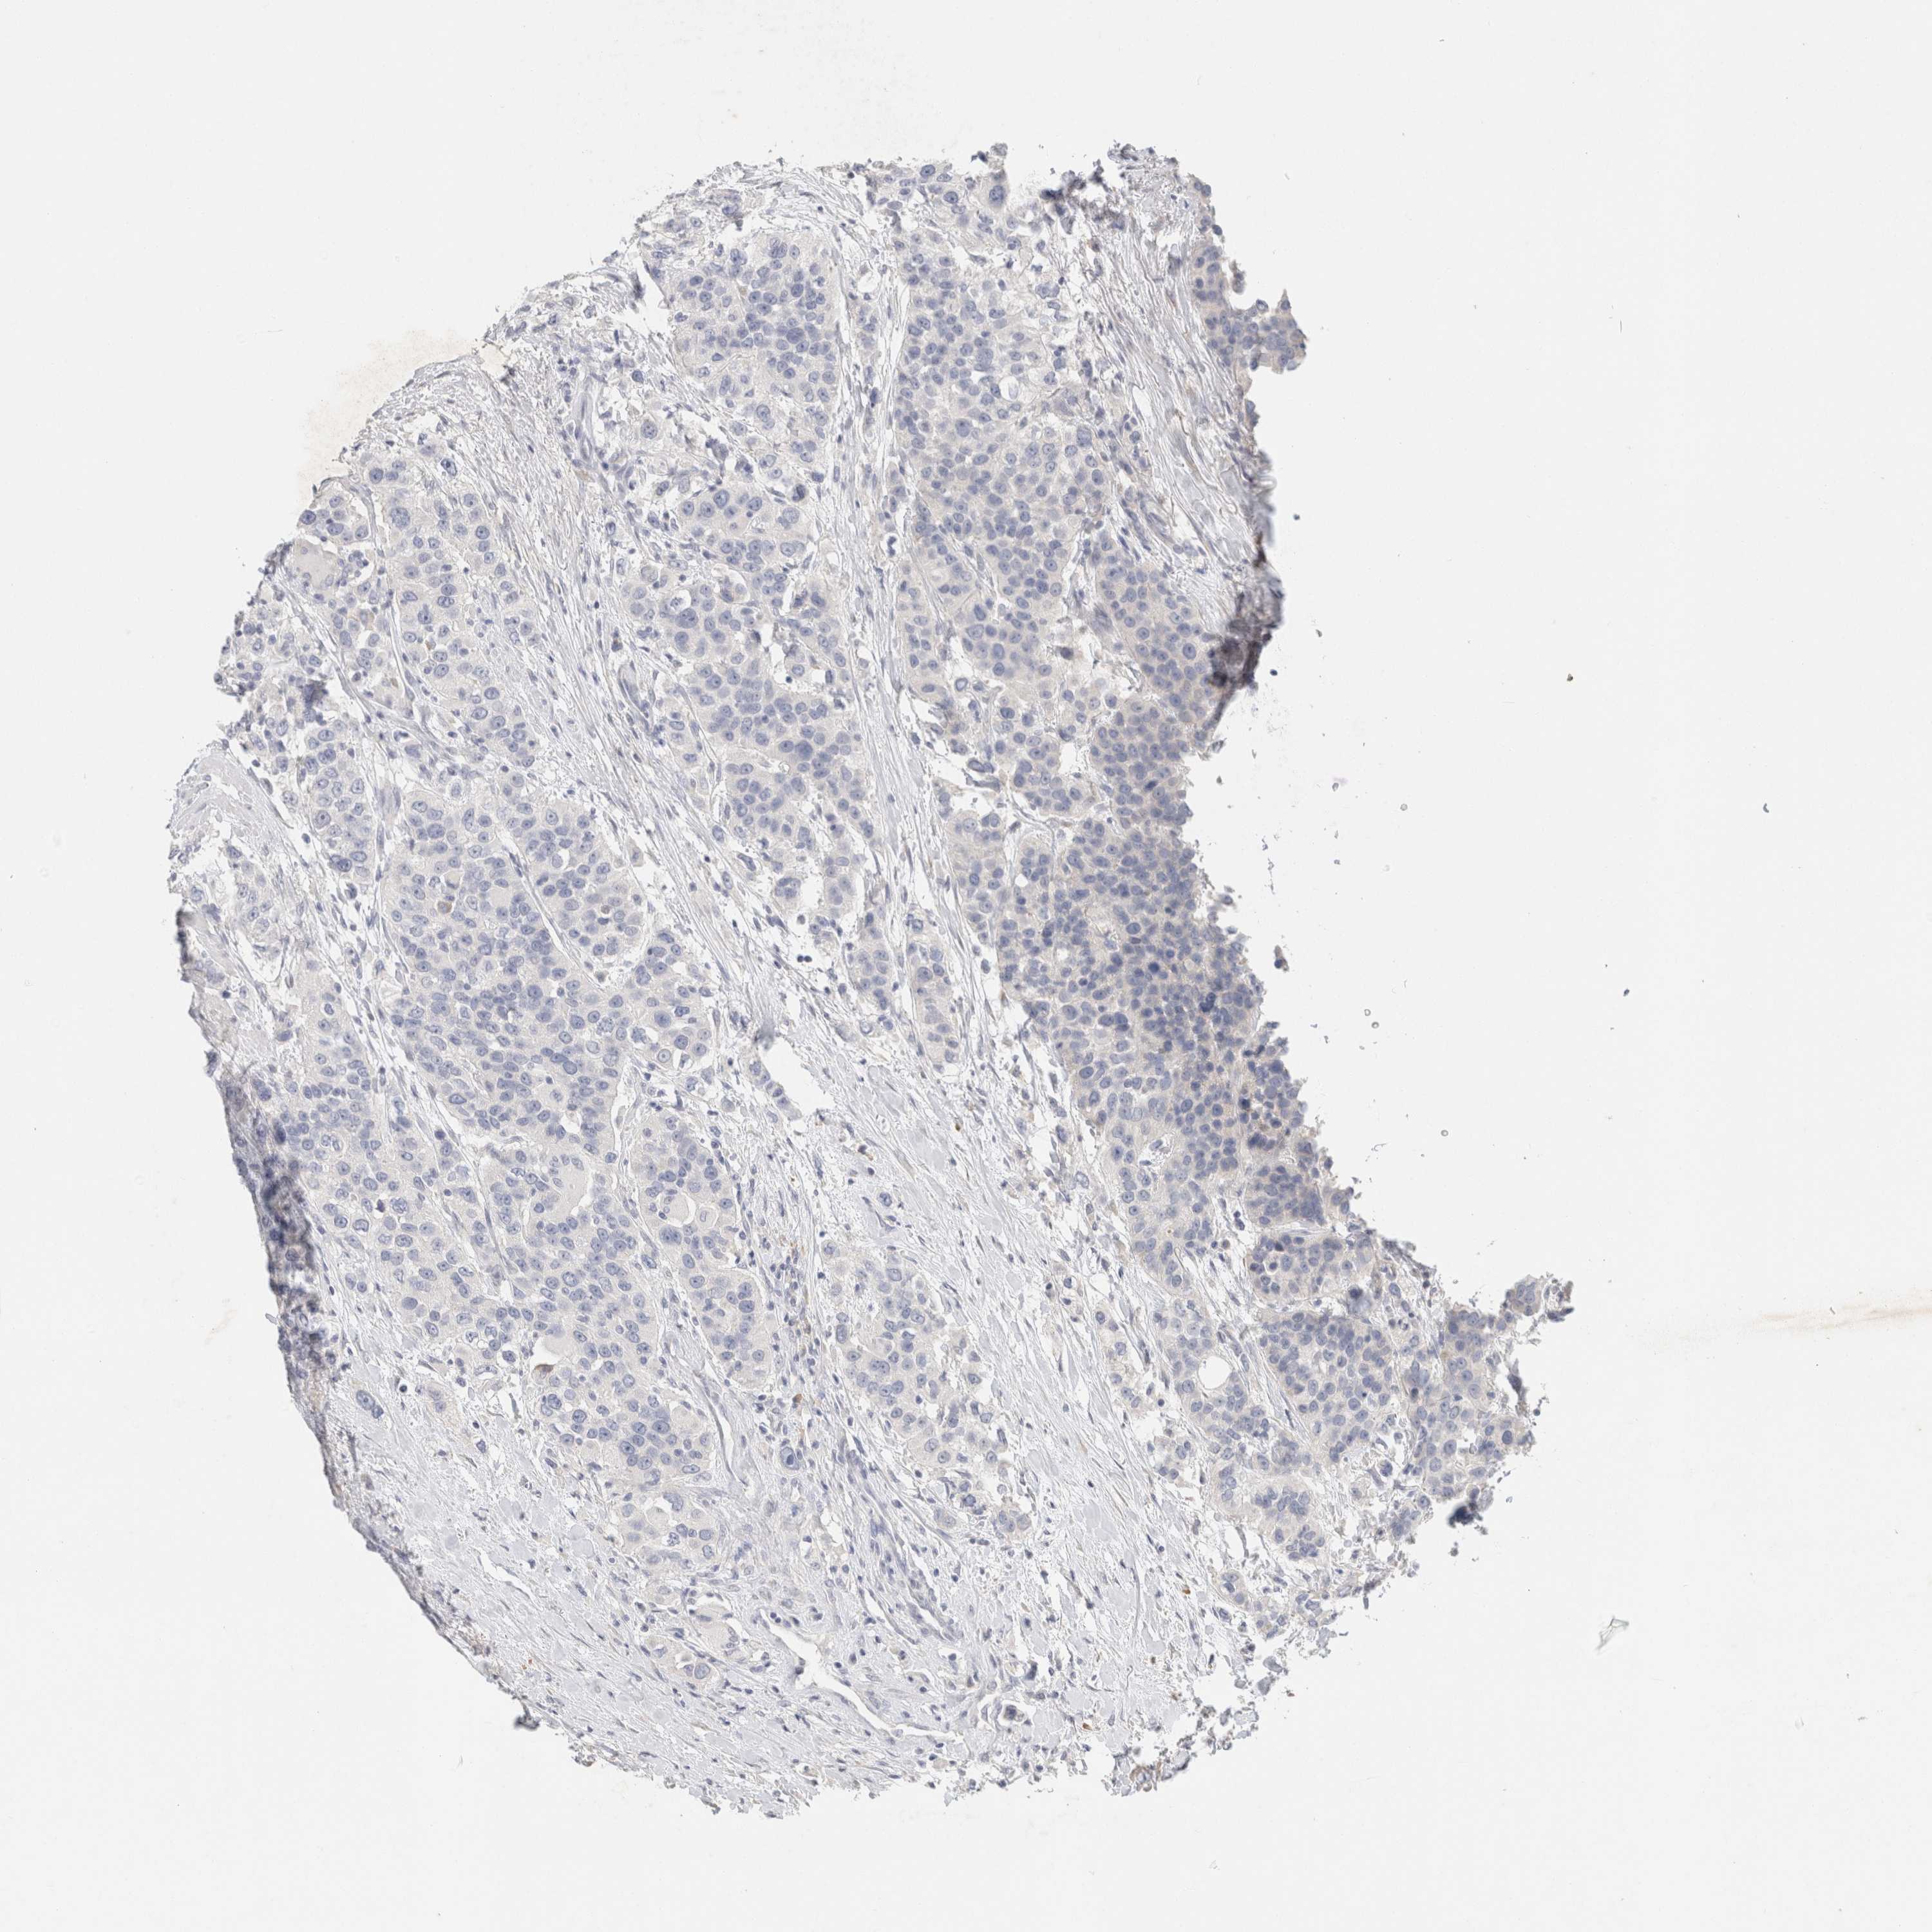

UROTHELIAL CANCER - Protein expressioni

A mouse-over function shows sample information and annotation data. Click on an image to view it in a full screen mode. Samples can be filtered based on level of antibody staining by selecting one or several of the following categories: high, medium, low and not detected. The assay and annotation is described here.

Note that samples used for immunohistochemistry by the Human Protein Atlas do not correspond to samples in the TCGA dataset.

Antibody stainingi

Antibody staining in the annotated cell types in the current human tissue is reported as not detected, low, medium, or high, based on conventional immunohistochemistry profiling in selected tissues. This score is based on the combination of the staining intensity and fraction of stained cells.

Each image is clickable and will lead to virtual microscopy that enables deeper exploration of all samples and also displays staining intensity scores, fraction scores and subcellular localization as well as patient and tissue information for each sample.

Antibody HPA022845

Antibody HPA023138

Antibody CAB010900

Antibody CAB012976

Staining

High

Medium

Low

Not detected

Intensity

Strong

Moderate

Weak

Negative

Quantity

>75%

75%-25%

<25%

None

Location

Nuclear

Cytoplasmic/membranous

Cytoplasmic/membranous,nuclear

Urothelial carcinoma, Low grade

Urothelial carcinoma, High grade